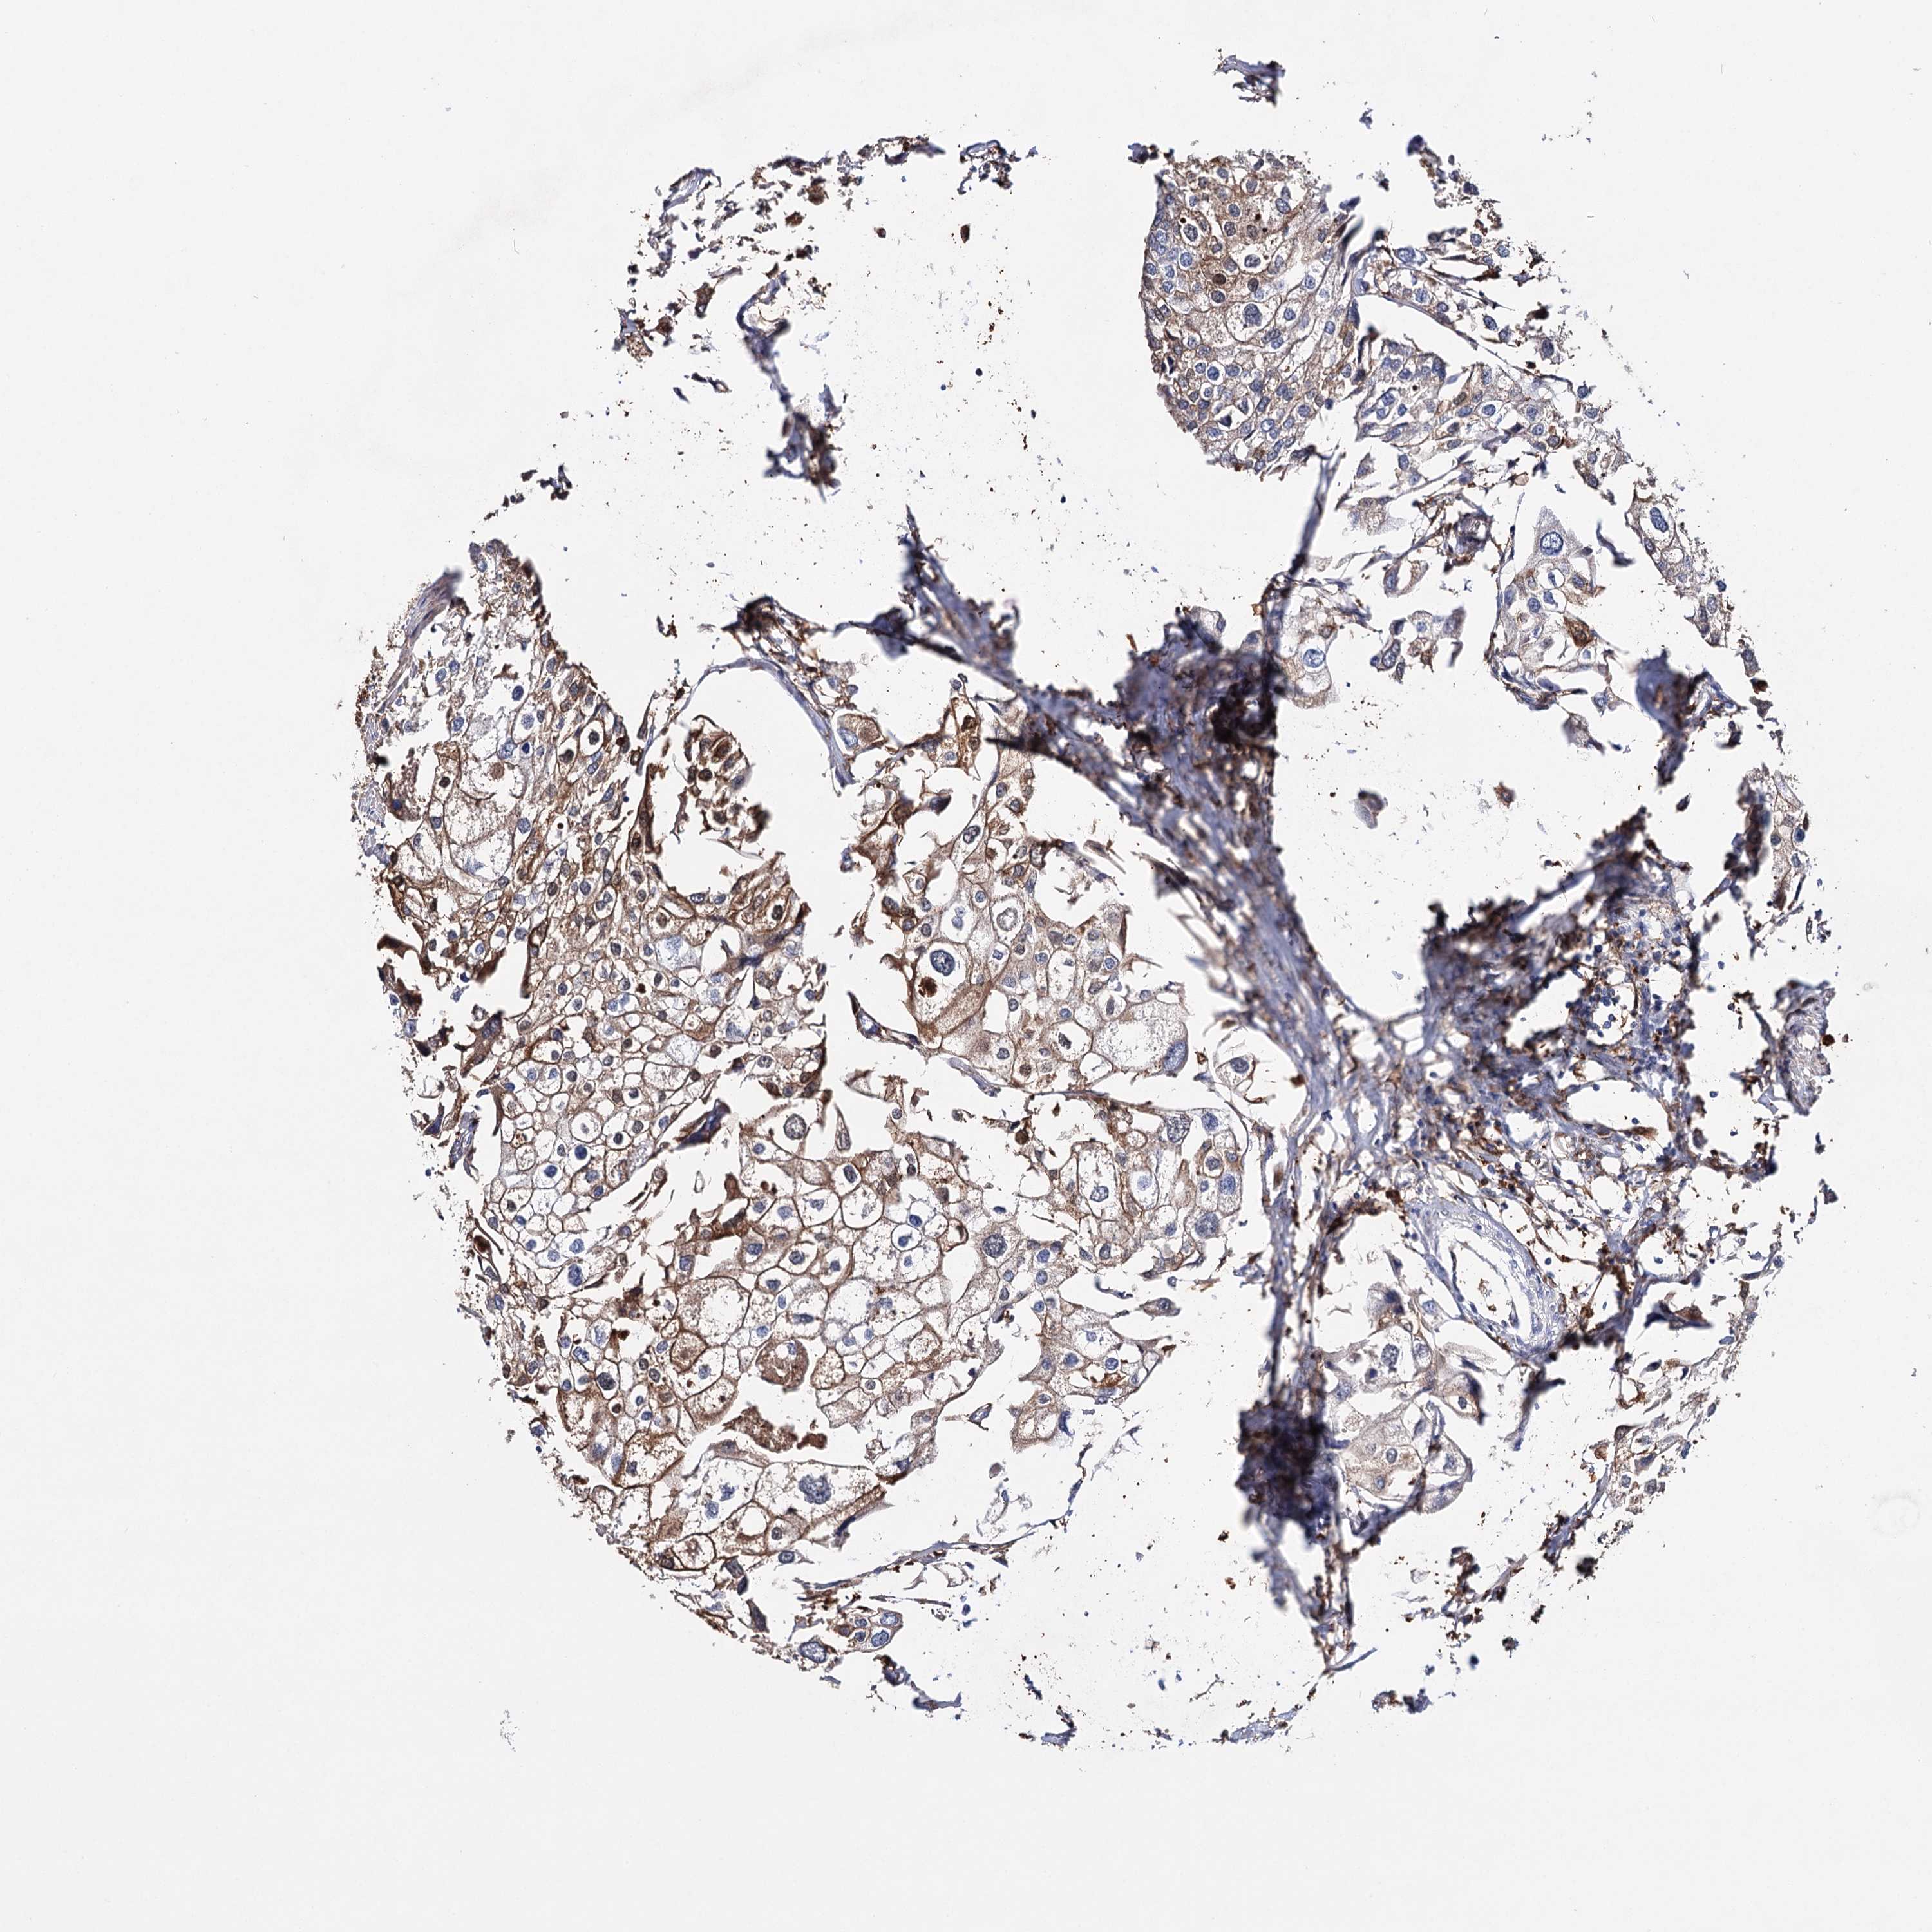

UROTHELIAL CANCER - Protein expressioni

A mouse-over function shows sample information and annotation data. Click on an image to view it in a full screen mode. Samples can be filtered based on level of antibody staining by selecting one or several of the following categories: high, medium, low and not detected. The assay and annotation is described here.

Note that samples used for immunohistochemistry by the Human Protein Atlas do not correspond to samples in the TCGA dataset.

Antibody stainingi

Antibody staining in the annotated cell types in the current human tissue is reported as not detected, low, medium, or high, based on conventional immunohistochemistry profiling in selected tissues. This score is based on the combination of the staining intensity and fraction of stained cells.

Each image is clickable and will lead to virtual microscopy that enables deeper exploration of all samples and also displays staining intensity scores, fraction scores and subcellular localization as well as patient and tissue information for each sample.

Antibody HPA037786

Antibody HPA038034

Antibody HPA038867

Antibody HPA038868

Staining

High

Medium

Low

Not detected

Intensity

Strong

Moderate

Weak

Negative

Quantity

>75%

75%-25%

<25%

None

Location

Nuclear

Cytoplasmic/membranous

Cytoplasmic/membranous,nuclear

Urothelial carcinoma, High grade

Urothelial carcinoma, Low grade

Urothelial carcinoma, NOS